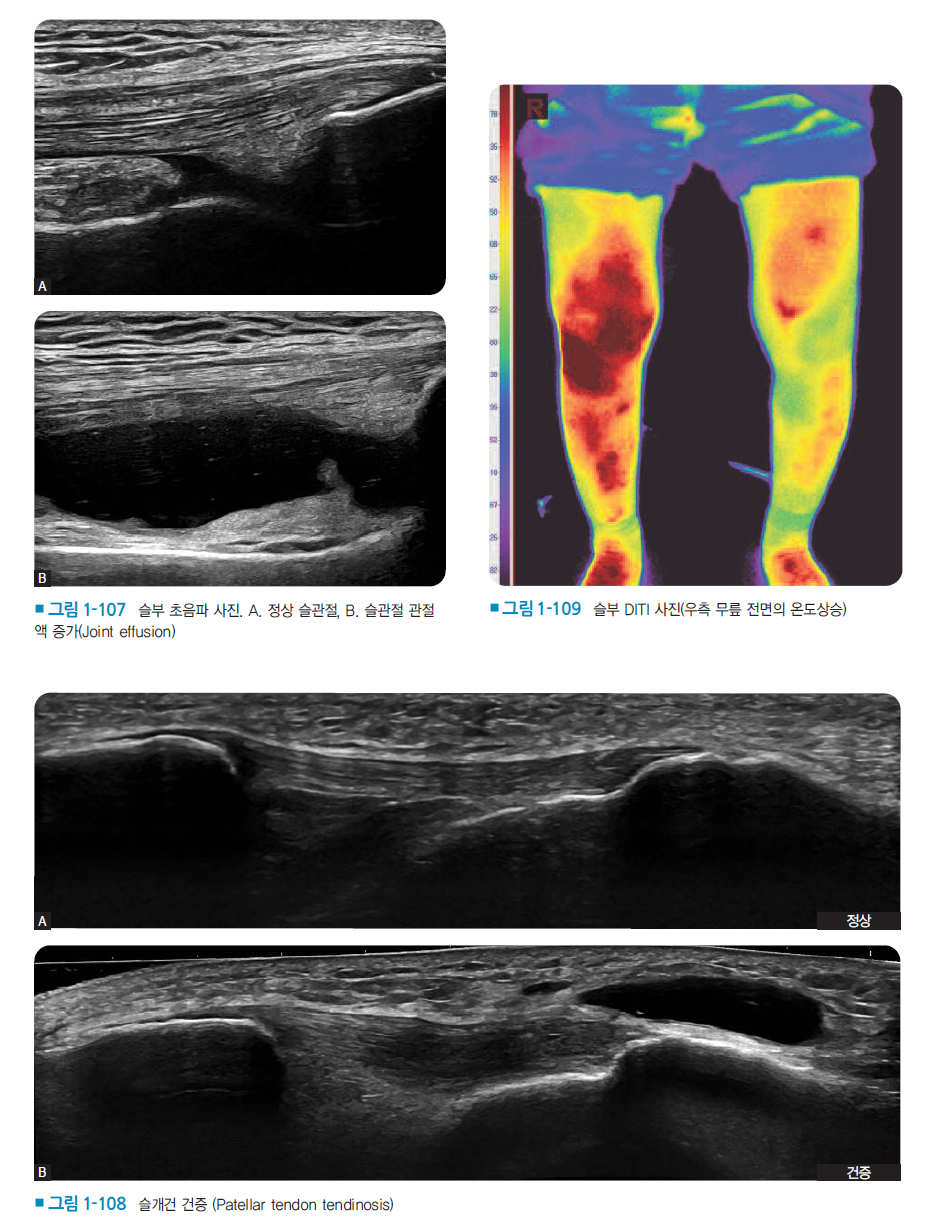

먼저 과학적 근거 기반의 총론 강화를 위해 의료인으로서 필수적인 감염 관리 지침과 수칙을 엄격하게 보완해 안전한 진료환경 조성의 근거를 마련했으며, 침 치료의 진통 기전에 관한 최신 국내·외 실험 및 임상연구 성과를 수록해 학술적 타당성을 확보했다. 더불어 초음파를 활용한 영상 진단 및 유도하 시술법, 레이저 치료기기 등 현대적 의료기기 활용법을 새롭게 수록해 임상 현장의 변화를 반영했다.